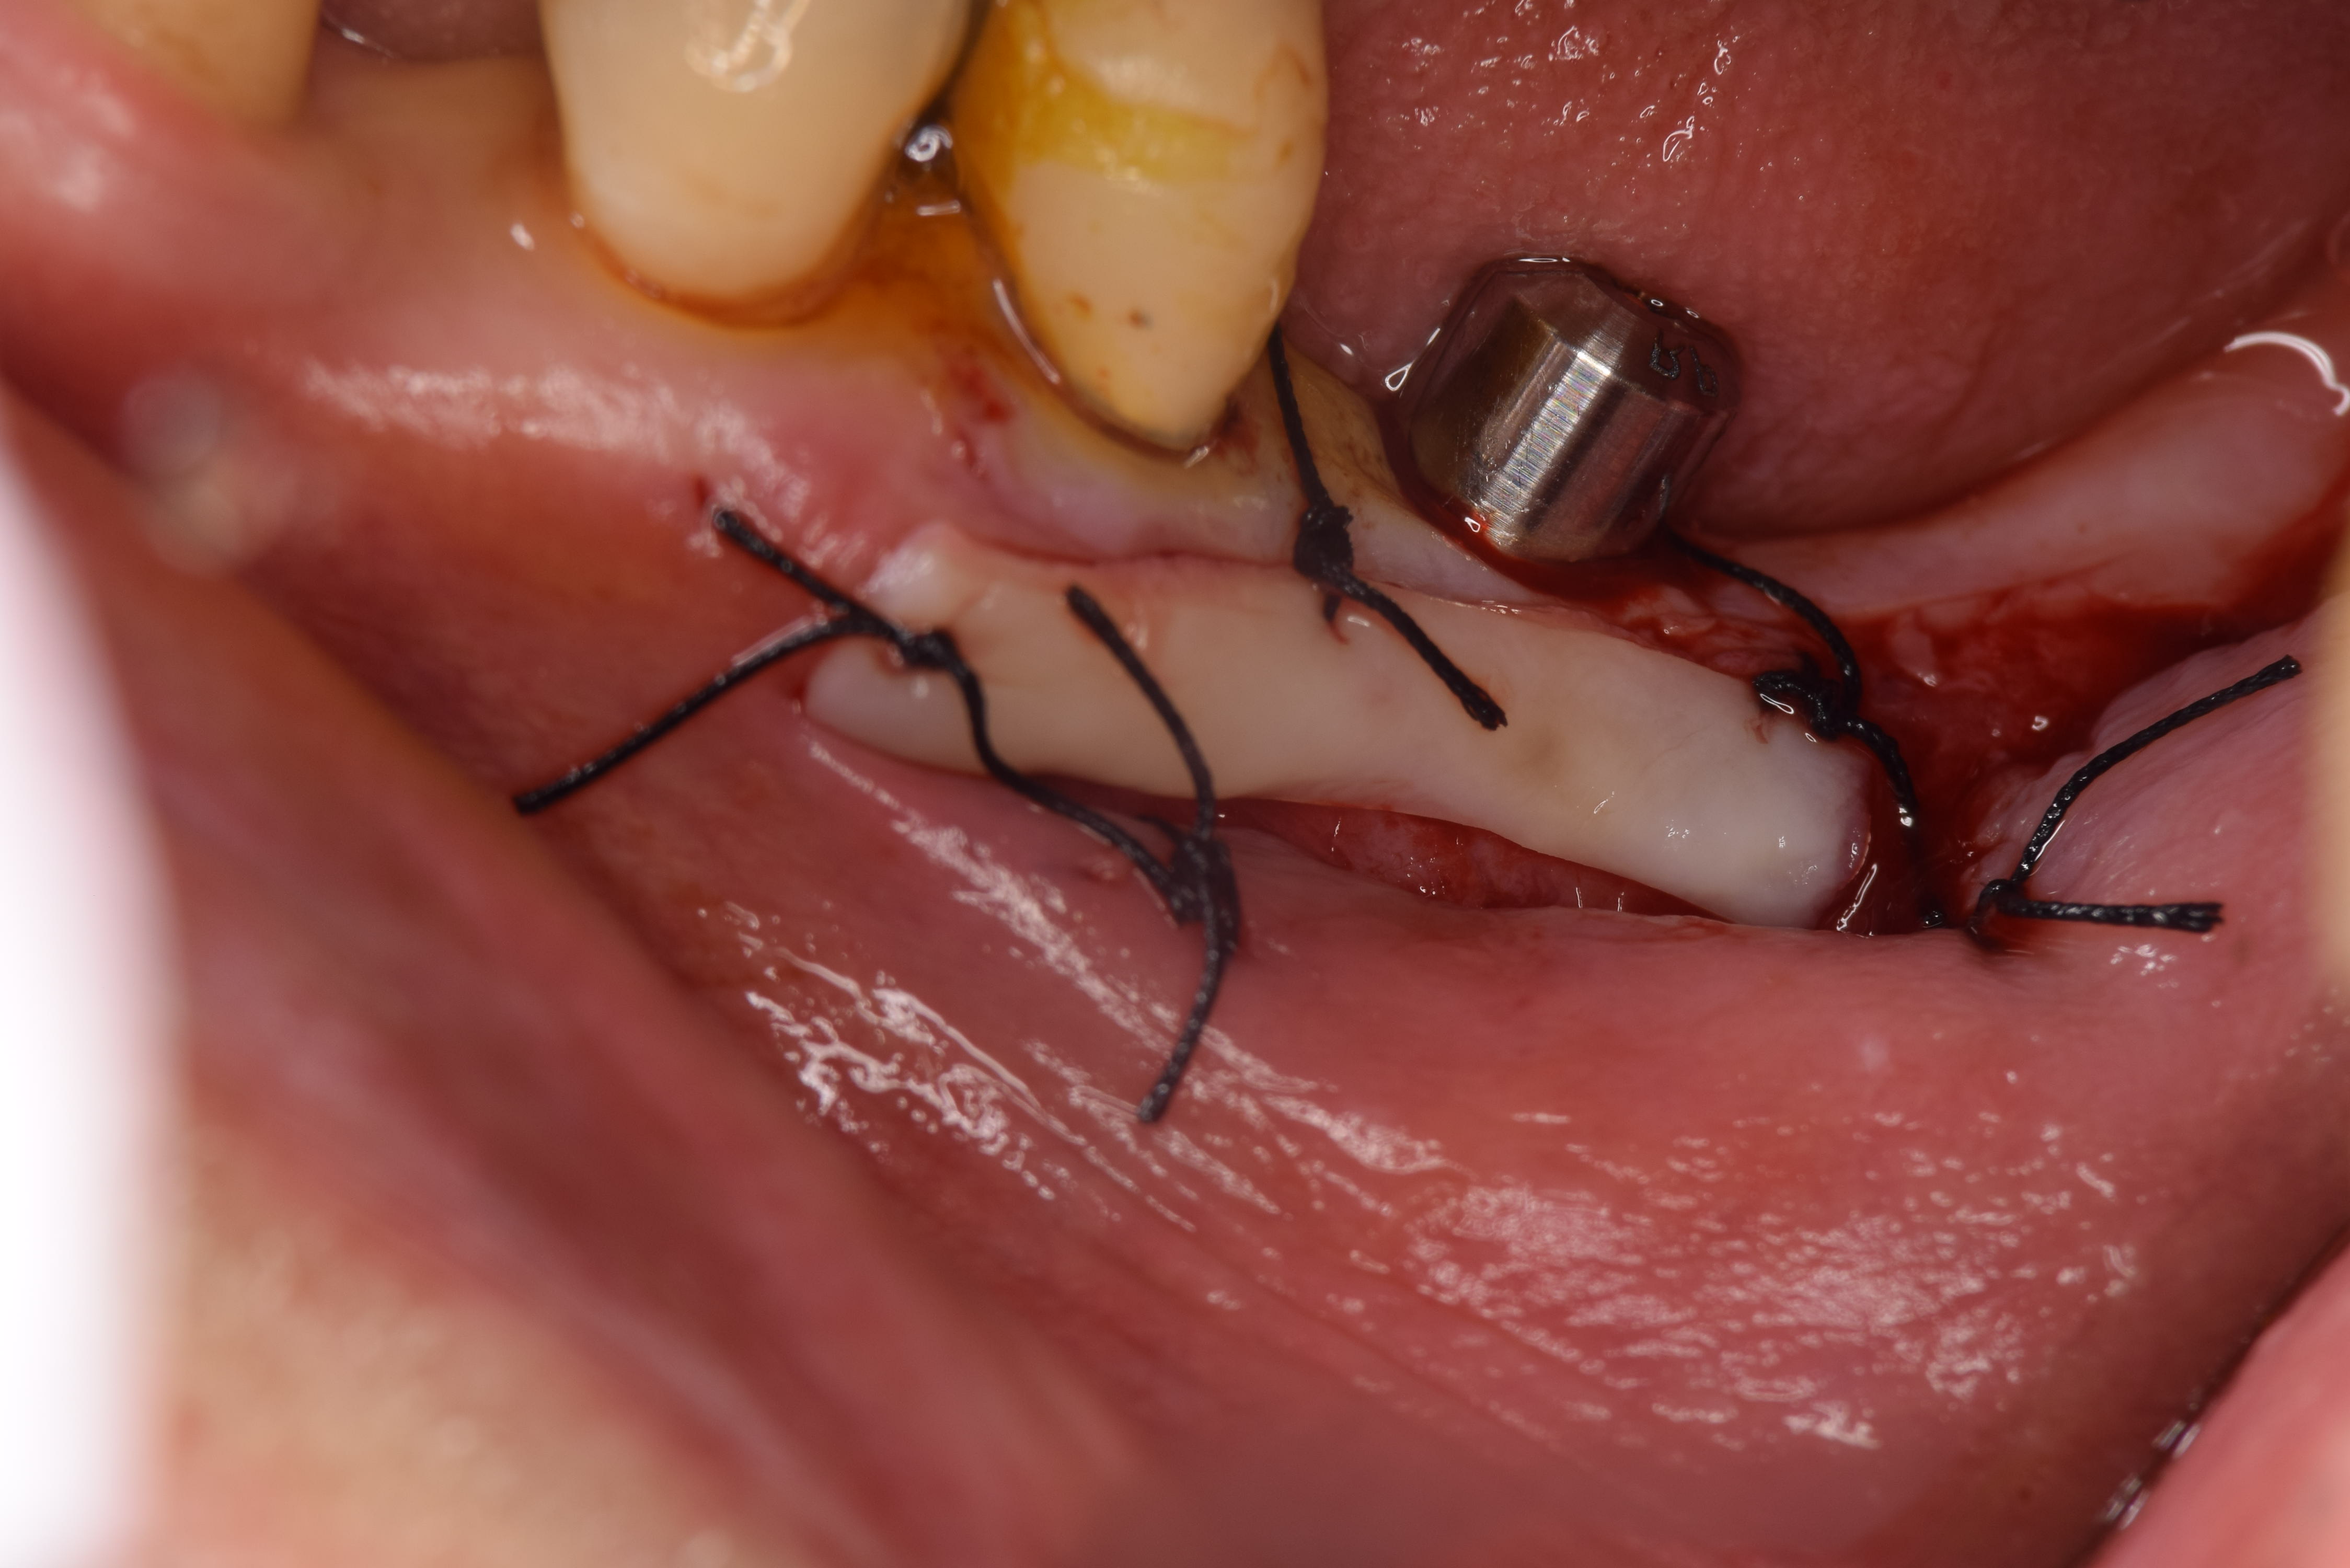

移植完了です。(ミラー像)

この処置を二次手術と2回に分けてしまうと手術が2回になってしまうため私は1度に同時に行っております。

同時に外科治療を行えば外科処置の回数を減らすことが出来ます。